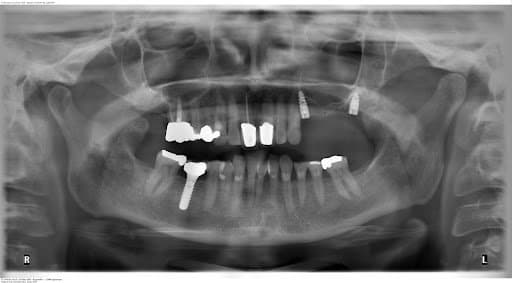

Planning of implant placement based on the CBCT

After the healing phase, a CBCT was taken to plan the implant placement and surgical technique. Due to the poor remaining bone volume and quality, it was decided to place the implants using a surgical guide to guarantee their accurate position in the areas where the bone quality was sufficient. Bone augmentation was discarded as a solution due to the complexity of this procedure for this specific clinical case. Alginate impressions were taken of both arches and sent to the dental laboratory, alongside the instructions for the implant positions, for design and fabrication of the surgical guide . A professional tooth cleaning was performed to prepare the oral cavity in a good hygienic condition for the operation.

A flapless surgical technique was chosen due to the fact that it is a minimal invasive procedure and there were appropriate clinical conditions to carry it out. After anesthesia was given, the surgical guide was positioned upon the supporting teeth and used to do the punch to remove the mucosa. A sequence of burs and their respective additional sleeves are used to gradually widen the bone (with a total of three drills, starting with the thinnest diameter). The implants were placed through the surgical guide and screwed into the bone holes up to the definitive bone height (this is a marking on the screw-in aid). The implants are fitted with a healing cap. Finally, a radiographic panoramic view control is done.

Postoperative OPG control